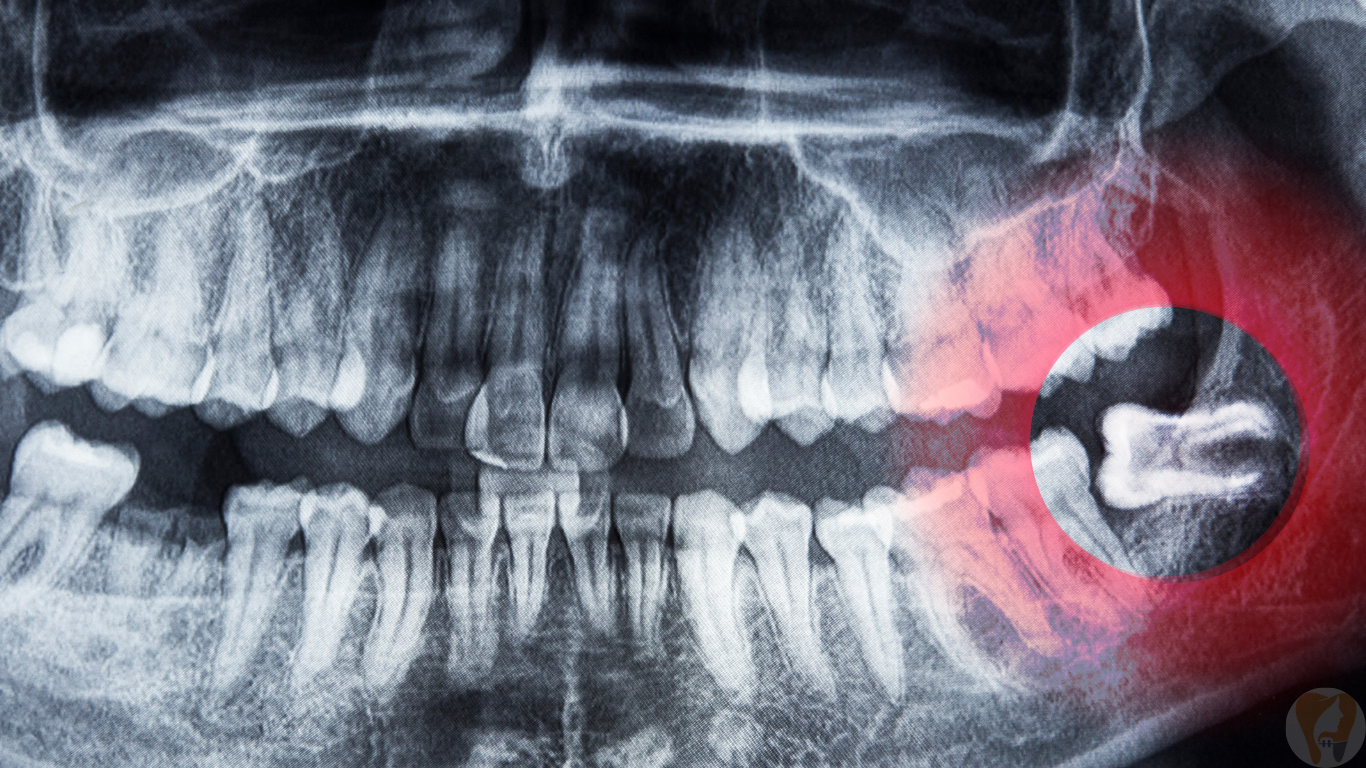

Wisdom teeth often emerge in the late teens or early twenties and can cause problems if they don’t erupt properly. Common issues include pain, swelling, infection, crowding, or damage to nearby teeth. At Janagond Skin & Dental Clinic, we specialize in evaluating and treating wisdom tooth problems through safe extractions and minor surgeries. Using advanced imaging and modern techniques, we ensure minimal discomfort and faster recovery, so you can get back to your daily routine without pain.

Examination & X-rays: Assess tooth position and complications.